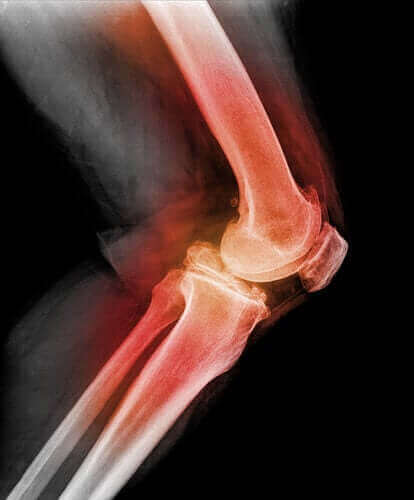

Анатомія та фізіологія

Занурення в людську анатомію та фізіологію допоможе вам зрозуміти, як працює ваше тіло. Ви дізнаєтеся таємниці кожної системи та кожного органу у вашому тілі, знатимете тканини і функції вашого організму, порушення в його роботі, і, найголовніше, як поліпшити ваше здоров'я - і життя.